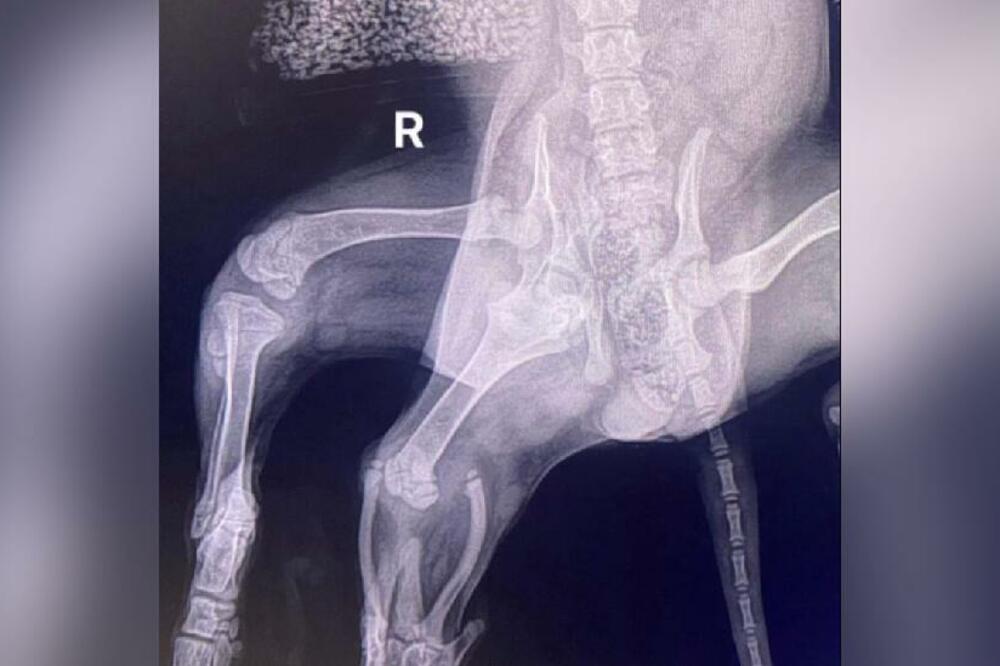

Ariel, a kerusha born with six legs who was left in a supermarket parking lot, has had a successful operation and two of her extra limbs have been removed.

This female cocker spaniel became famous when news broke that she was found in Pembrokeshire, UK in September.

"The vet who performed the first examination noticed that, in addition to two extra hind legs, Ariel also has two vaginas," said 42-year-old Lawlor.

"Since she has two hips on one side of her body, her pelvis has not developed properly.

"As a result, her regular right hind leg had no muscle tone, so there was a possibility that she would remove that as well.

Ariel, who was named after the cartoon character The Little Mermaid because her two hind legs partially joined resemble the Disney character's tail, underwent surgery at Langdord Clinic in Somerset on Thursday.